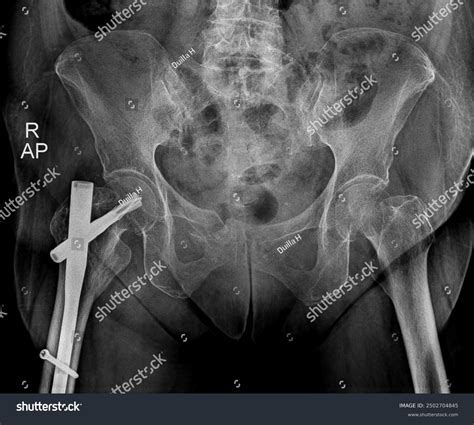

To define Open Reduction Internal Fixation, we must break the term down into its two primary components: reduction and fixation. "Open reduction" refers to the surgeon making an incision to physically visualize the fracture site, allowing them to realign the displaced bone fragments. "Internal fixation" refers to the use of hardware—such as metal plates, screws, rods, or pins—that is placed inside the body to hold the bone in its corrected position while it undergoes the natural healing process.

This procedure is typically reserved for fractures that are unstable, comminuted (shattered into multiple pieces), or involve a joint surface. By utilizing internal hardware, surgeons can provide the stability that external methods simply cannot offer, effectively bridging the gap between the injury and full mobility.

4. Fixation: Metal plates, screws, or intramedullary nails are attached to the bone to lock the fragments in place.

Recovery time varies depending on the location of the fracture and the patient’s overall health. Patients may expect a period of restricted weight-bearing, followed by a gradual return to normal activity. Imaging tests, such as X-rays, are conducted at regular intervals to monitor the progression of bone growth around the hardware.